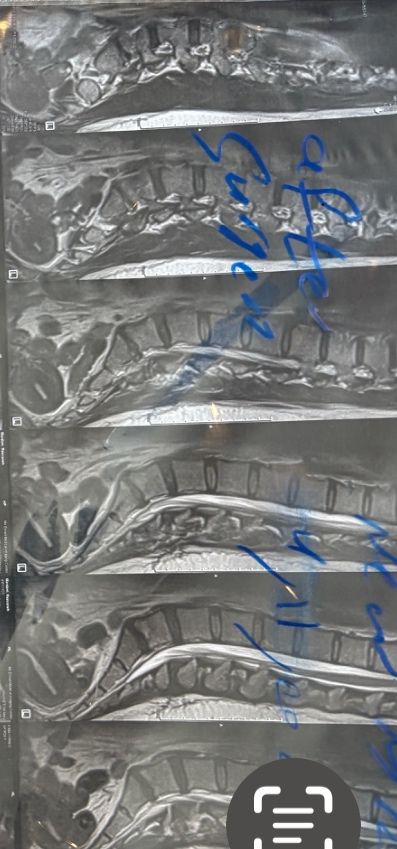

41 years old man presented to my clinic in October 2023 with acute and sever R neck pain with radicular pain to his R upper extremity along C6 dematom since 2 weeks ago. Examination didn’t show any upper motor signs. Was suggested urgent surgery

I ordered EMG/ NCV : showed mild R C6, C7 irritation without any active axonal loss

In his MRI was reported R. para R. IVF Massive extrusion. I decided to control his pain and manage this patient with reevaluation of patient every other session. For 5 sessions i just used acupuncture and laser and IFC and mild adjustments to his R. T3-T7 and mild arthosteem to above and below involved segment. Cervical adjustment considered contraindicated for this patient. From session 6th- 8th i started to use mild/gentle cervical decompression. He used soft cervical collar all the time. His pain decreased by 80 percent

I gave him cervical traction pump to be used 3-5 times per day at home for the next 3 months and i released the patient. He was evaluated every week once for one month and after that every 2 weeks. After 3 month I repeated MRI. Size of the herniated disc was reduced greater than 50 percent. Asked him to do another mri in 6 months

In general: Precise selection of the patients, examination,diagnosis, plan of management, reevaluation and treatment can be done by doctors of chiropractic for the patients with spinal disc herniation and stenosis Moreover giving reasonable time to these kind of patients under direct supervision by their chiropractic doctors can prevent unnecessary surgery. Proper selection of these kind of patients is another important fact that can be done precisely by chiropractors.

MRIs before and after proper management of this patient: